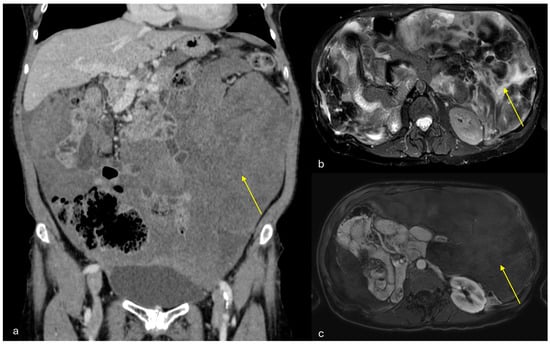

3.1.2. Peritoneal Mesothelioma

3.1.3. Peritoneal Localizations of GIST–Peritoneal Sarcomatosis

3.1.4. Angiomyofibroblastoma

3.1.5. Peritoneal Lymphomatosis

3.1.6. Mesenteric Metastases from Ileal Neuroendocrine (Carcinoid) Tumors